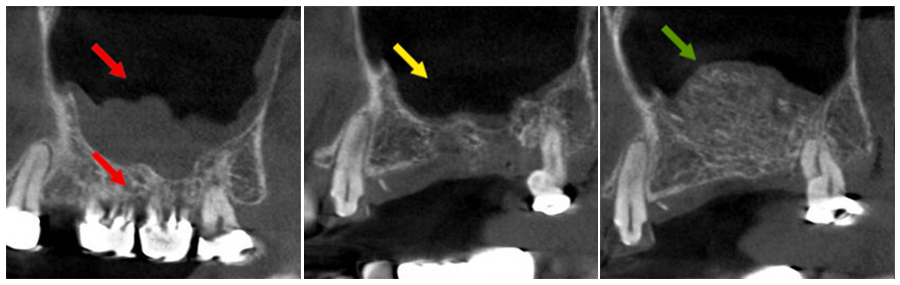

病人於外院進行彈夾牙治療後牙根斷裂,合併鼻竇穿孔,鼻竇黏膜嚴重感染。

- 紅色箭頭:下方牙齒牙根斷裂,鼻竇黏膜感染增厚。

- 黃色箭頭:移除患齒後進行清創,拔牙後使用膠原蛋白修補,兩個月後恢復清澈鼻竇(影像區為黑色)。

- 綠色箭頭:鼻竇恢復健康後,進行上顎竇提升手術補骨,恢復上顎竇正常骨量,準備進行人工植牙手術。